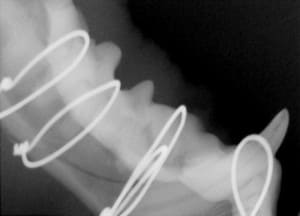

Crowns are placed on fractured teeth to provide the strength to the tooth structure. This is often performed on working dogs or pets who need their teeth for specific activities. The crowns are made of non-precious metal and require one episode of anesthesia to prepare the tooth and create the molds for crown fabrication, and a second anesthetic episode to fit and cement the crowns.